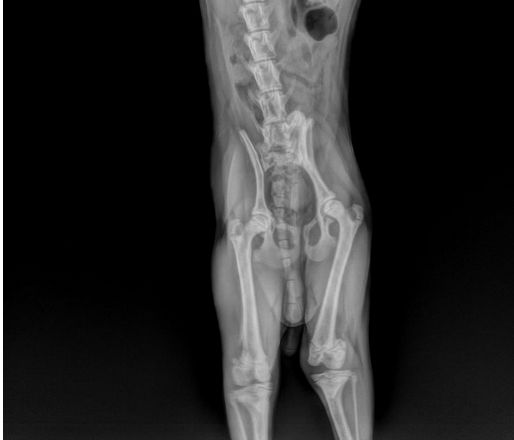

当患犬出现破行时,通过手触诊整个患肢无痛觉应重点怀疑本病,对出现明显破行者,用手检查髌骨可见明显脱位现象。有条件的动物医院应通过X光诊断,在X光正位片可见髌骨位于股骨的内侧或外侧,而不在股骨滑车中,同时可见滑车沟变浅、胫骨近端弯曲转位和股胫关节成角异常。当幼犬的髌骨钙化不全时,其移位则很难显示。在X光侧位片上,可见髌骨不在滑车沟内而是与股骨髁重叠。